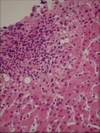

What does chronic inflammation look like?

Characterised microscopically which are much more variable than acute inflammation.

- Macrophages

- Lymphocytes

- Plasma cells

- Eosinophils

- Fibroblasts/ Myofibroblasts

- Giant Cells